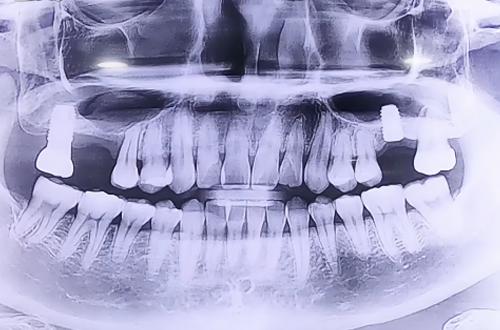

AFTER

반대편 오른쪽 위에도 뼈가 조금 남아있는 상태였기 때문에 상악동거상술을 동반하여 뼈이식을 진행해 드렸습니다.

뼈이식 이후 임플란트까지 당일 식립해 드렸으며 뼈이식의 양이 많기 때문에 뼈들이 단단해지는 기간인 6개월 이상 충분히 기다린 뒤에 큰 어금니 모양의 이를 제작해 드릴 예정입니다.

예쁜 보철이 완성되면 다음 진료일지로 찾아뵙도록 하겠습니다. ^^!